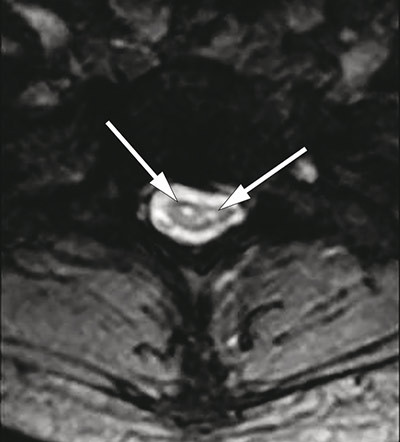

MR av ryggmargen viste markert atrofi fra nivå C4 til Th2 og to langsgående symmetriske T2-vektede høysignallesjoner fra nivå C2 til Th2 (fig 3, fig 4), lokalisert til området for anteriore horn i medulla. Forandringene ble ikke oppfattet å være forenlig med syringomyeli, demyeliniserende plakk, tumor eller transvers myelitt. Det var normale funn ved MR caput.

Det er publisert flere kasuistikker og noen få MR-studier vedrørende O’Sullivan-McLeod-syndromet, men ingen oversiktsartikler. I 1989 publiserte Gaio og medarbeidere (11) en serie med fem pasienter. MR av cervikal- og torakalcolumna ble gjennomført hos fire pasienter med T1- og T2-vektede bilder. På T1-vektet serie ble det beskrevet avflating av medulla fra C5 til Th1 og normale forhold fra C1 til C4. Funnet ble tolket som segmental spinal atrofi av medulla. Signalforandringer i medulla ble ikke påvist.

Petiot og medarbeidere (12) publiserte i 2000 en kasuistikk av en 41 år gammel kvinne med O’Sullivan-McLeod-syndromet. Pasienten hadde over en periode på 20 år utviklet en langsomt progredierende asymmetrisk svakhet i begge hender. Det var ingen nevrologiske sykdommer i slekten. MR av cervikalcolumna avdekket symmetriske høysignallesjoner på T2-vektede bilder, svarende til et område av forhorncellene som strakte seg fra nivå C6 til C7. Diameteren av cervikalmedulla ble vurdert som normal.

O’Sullivan-McLeod-syndromet er en sjelden form for distal spinal muskelatrofi med forholdsvis god prognose. Diagnosen bygger på kliniske og nevrofysiologiske undersøkelser og karakteristiske MR-forandringer med segmental atrofi i cervikalmedulla og høysignallesjoner i området svarende til fremre motornevron.